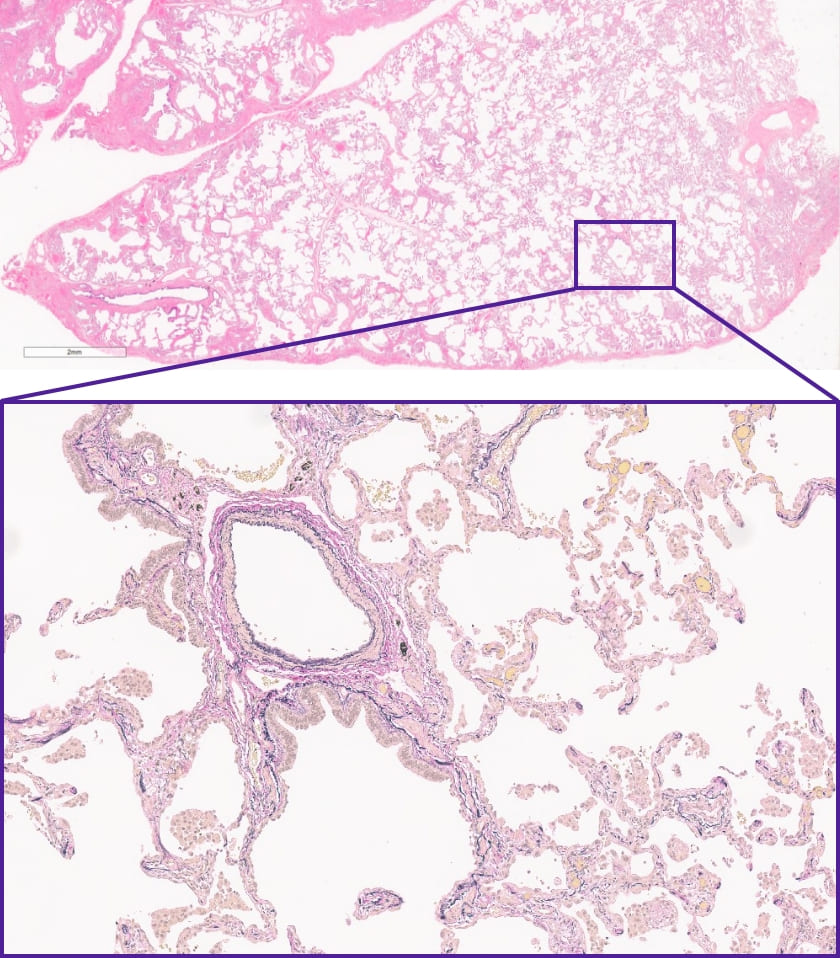

この症例の外科生検検体は?

DATA 1| X 線検査結果